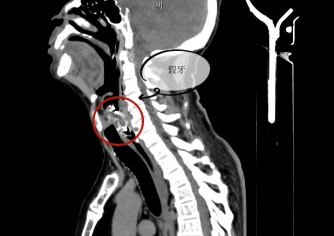

65岁的王叔叔吃饭时不慎误吞整排带铁钩假牙,咽喉痛,进食困难,就诊当地医院,用胃镜、食道镜等多次尝试后无法取出,马上转诊至我院。经过喉镜、颈部CT等相关检查,发现异物为钩状体积大假牙,横跨喉咽及食道,钩体已深入食道造成损伤,局部组织水肿明显,异物若未及时取出将出现呼吸梗阻,合并感染将出现脓肿可能,生命危在旦夕。

术中看到异物为大体积钩状,爪钩像八爪鱼一样横跨喉咽部及食道入口,钩体已致食道穿孔,在耳鼻咽喉科杨心青主任医师、陈勇主任医师、王晓燕副主任医师、许玲玲医师及麻醉科丘春华副主任医师的配合下,通过直达喉镜、弧形喉镜、扩展喉镜联合食道镜多次更换配合“接力”,成功取出异物,避免了颈外入路取异物的创伤。术后王叔叔因喉部水肿送入重症医学科进一步治疗,3天后顺利出院。

卡在王叔叔咽喉中的假牙终于被取出